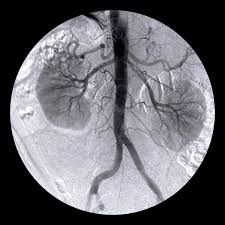

Dirigente Medico di ruolo presso U.O.C. Chirurgia Vascolare ed Endovascolare Ospedale San Giovanni di Dio e Ruggi d’Aragona di Salerno. Pratica attività ambulatoriale, laboratorio di diagnostica ultrasonografica, diagnostica angiografica e attività di sala operatoria (chirurgia open ed endovascolare). L’attività chirurgica tradizionale ed endovascolare comprende il trattamento delle lesioni stenotiche/ostruttive dei tronchi sovraortici (carotidi), lesioni stenotiche/ostruttive delle arterie periferiche e viscerali, degli aneurismi dell’aorta e aneurismi periferici e viscerali (sia in elezione che in urgenza), inoltre l’attività chirurgica comprende il trattamento della patologia venosa (vene varicose/varici) secondo le tecniche chirurgiche classiche (es. stripping) e moderne (laser, radiofrequenza, scleroterapia maggiore), scleroterapia minore di teleangectasie e vene reticolari (estetica vascolare).